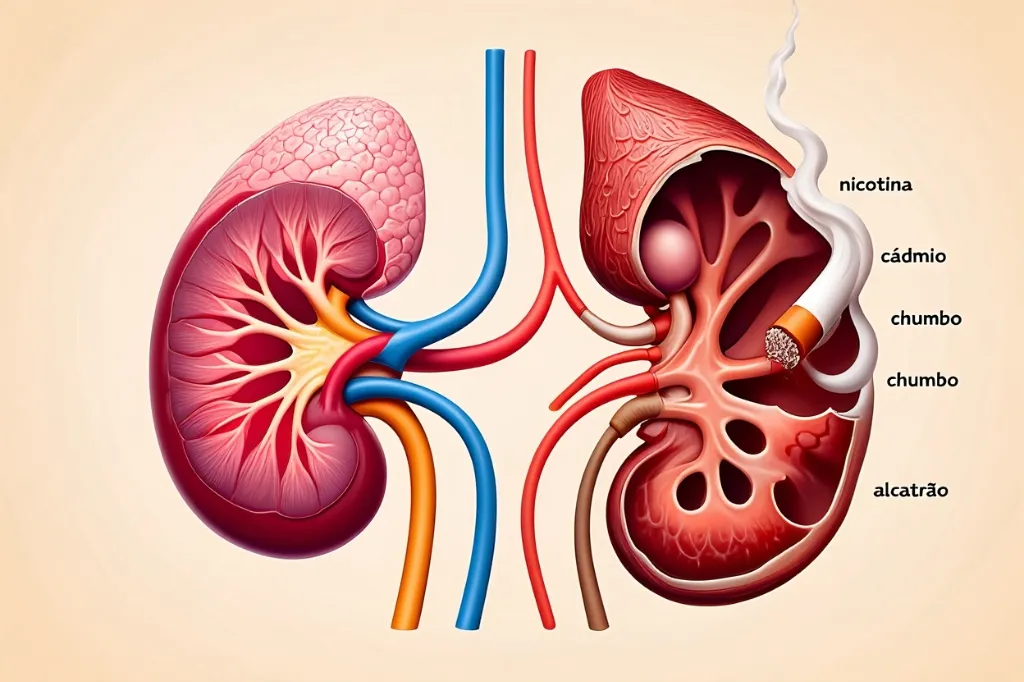

Descubra como o tabagismo acelera a falência renal e aumenta os riscos em pacientes diabéticos.